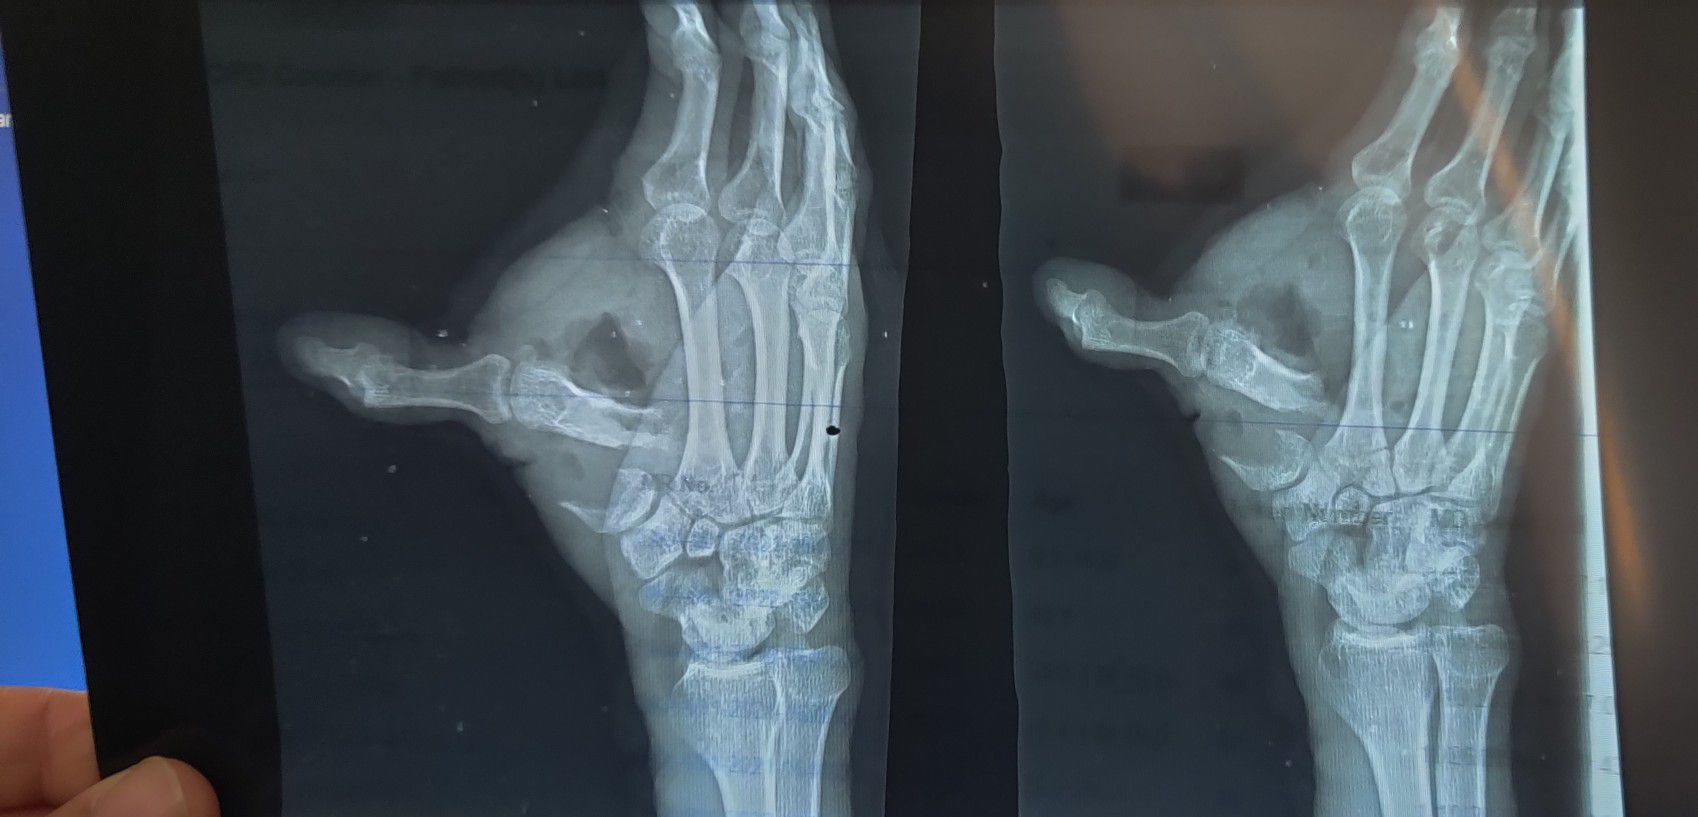

Traumatic injury to hand with fracture and dislocation of 1st metacarpal

Injury

Fracture

Hand

Rta